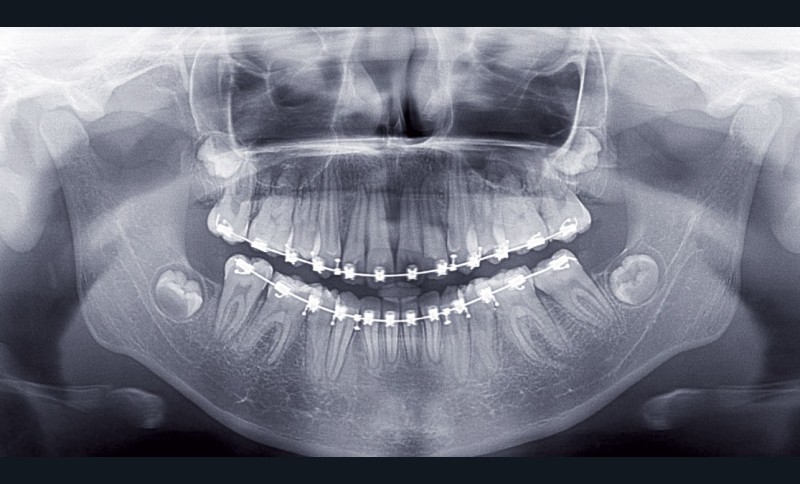

Le site des extractions s’est porté sur les secondes prémolaires. La justification de ces extractions passent par la résolution de l’encombrement sans effondrer le prémaxillaire.

La résolution de la classe II squelettique n’est aucunement recherchée au travers des extractions mais par une mécanique interarcade.

Ce cas a été conjointement suivi par les Drs Le Gall, Bachet et Dameron.